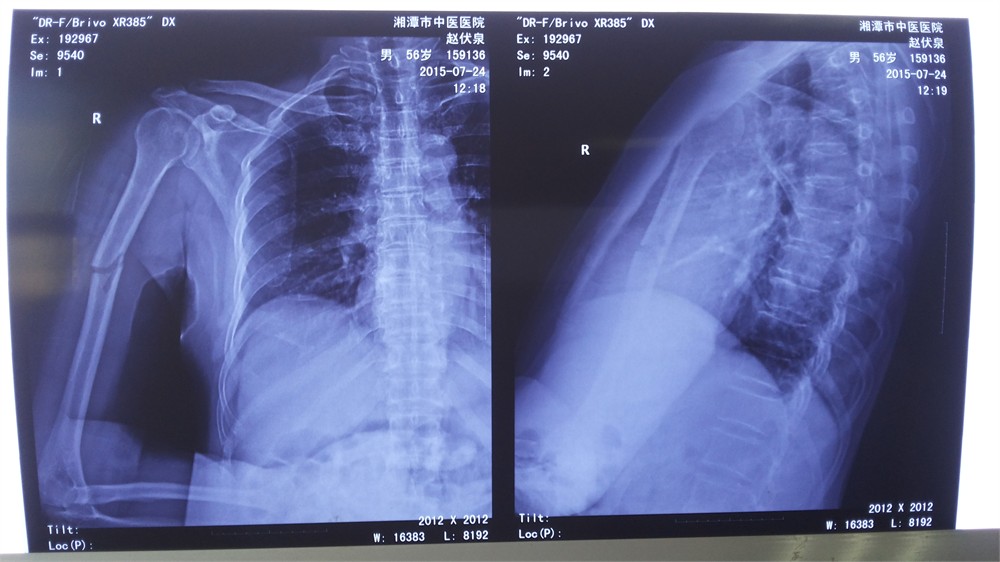

在原來(lái)固定的基礎(chǔ)上,予以上肢外展架將右上肢托起,外側(cè)成角完全糾正,骨折端及小骨片解剖復(fù)位,對(duì)位對(duì)線好。見下圖:

對(duì)于這一類肱骨骨折,手法復(fù)位最大限度地減少了骨折部位的繼發(fā)創(chuàng)傷,相對(duì)手術(shù)治療,并發(fā)橈神經(jīng)損傷概率低。復(fù)位并夾板外固定對(duì)血運(yùn)無(wú)破壞,具有愈合時(shí)間短、愈合率高、功能恢復(fù)好、并發(fā)癥少、費(fèi)用低廉等優(yōu)點(diǎn)。